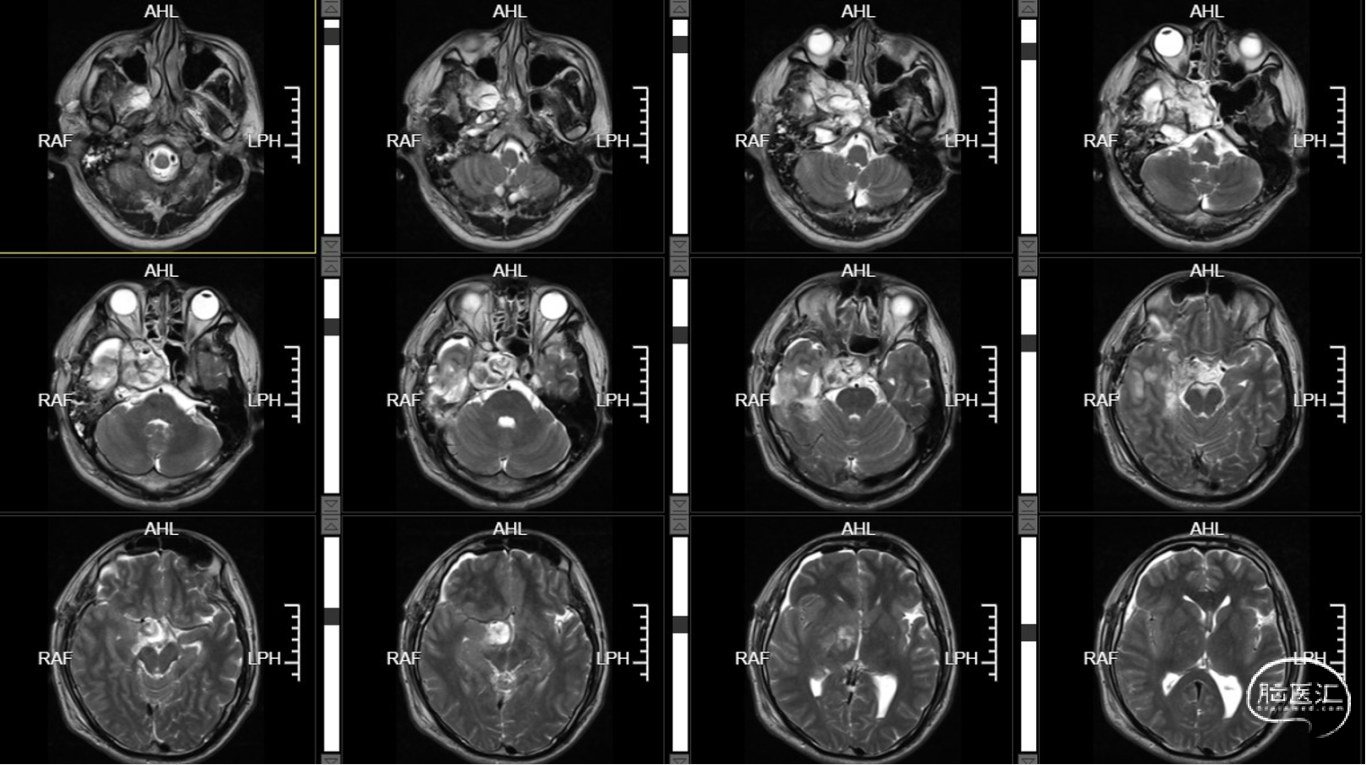

外院MR示:右侧颞底、桥小脑角区及鞍内占位,考虑表皮样囊肿伴破裂可能。